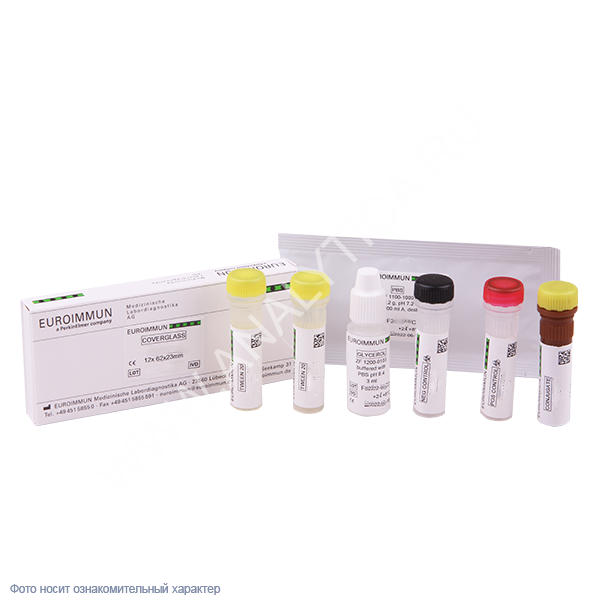

Медицинские снимки и изображения опоясывающего герпес вируса